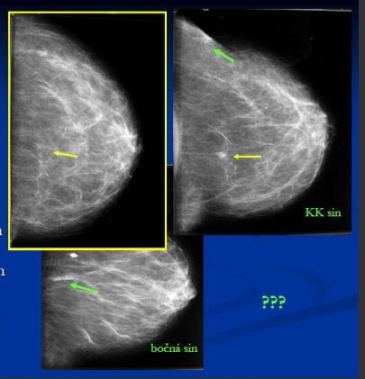

- Pouze v MDL projekci zachyceno 4mm ložisko v HQ – popsáno jako intramam.LU, nemá korelát v KK

- Ve FN HK před výkonem před lokalizací vodičem zhotoveny KK a bočná projekce sin

- Ložisko v KK projekci (CCB Hi: duktální Ca)